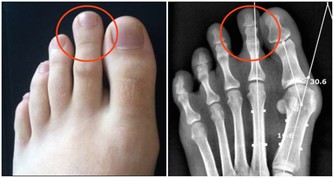

二十五、齦上潔治和齦下刮治之後,很多人會發現牙齒的縫隙變大了,很多人就會誤解為洗牙會把縫隙洗大了。

其實這是一種錯誤的想法,洗牙前沒有感覺到牙齒的縫隙是因為那些縫隙裡面填滿了牙結石,舌頭舔上去感覺不到,當結石清除后,縫隙就會顯露出來。